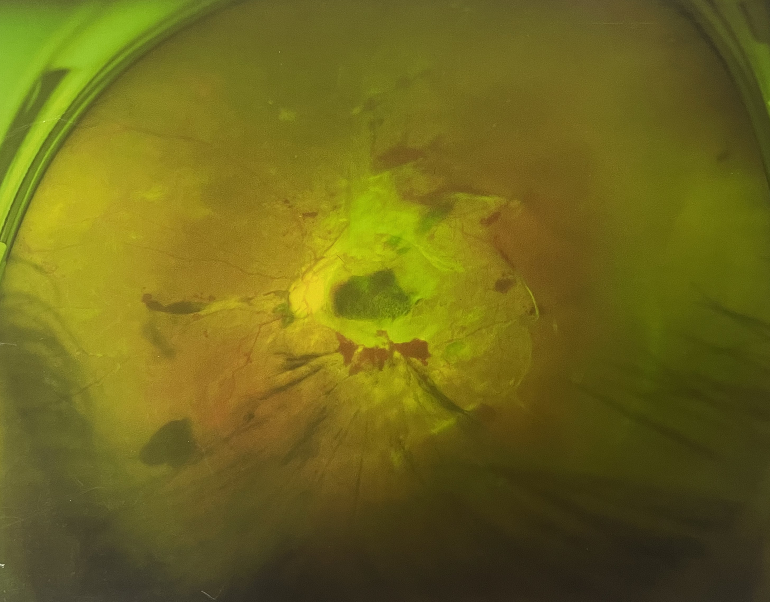

4個月前的左眼

左眼發(fā)展到糖尿病視網(wǎng)膜病變VI期

由于王女士的左眼沒有聽從醫(yī)生盡快做手術(shù)的建議,一直耽誤,從4月前的0.4視力逐漸下降到僅剩眼前手動,導(dǎo)致左眼發(fā)展到糖尿病視網(wǎng)膜病變VI期(屬于6期糖網(wǎng)中的晚期),已經(jīng)產(chǎn)生大量新生血管+纖維增值+廣泛牽拉性視網(wǎng)膜脫離,由于耽誤了病情,且病情發(fā)展異常迅速,導(dǎo)致目前左眼連保住眼球都很困難。

“而如果4月余前,左眼及時手術(shù)(當(dāng)時左眼病情比右眼輕,增殖膜還未累及黃斑),左眼將恢復(fù)的比右眼還好,甚至可以恢復(fù)到0.8或1.0,而現(xiàn)在連保住眼球的機(jī)會都很渺茫”,張小虎醫(yī)生表示實(shí)在可惜。